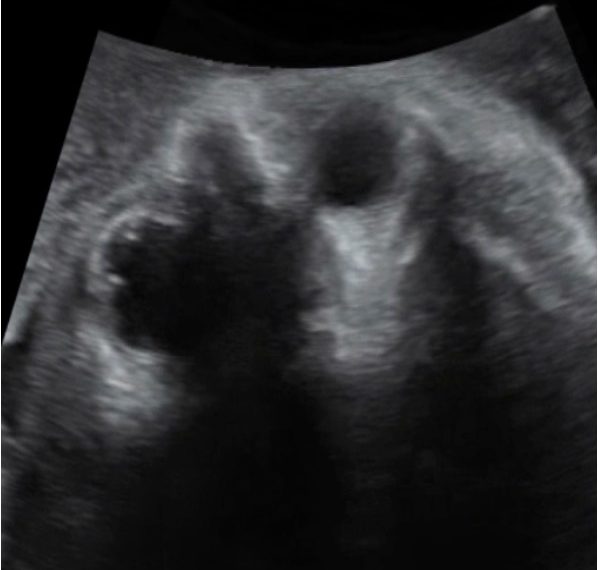

How To Do Dicembre 2023: ecografia in sala parto

Cari soci, questo mese un nuovo video "How to do", dedicato all'ecografia in sala partoGrazie a